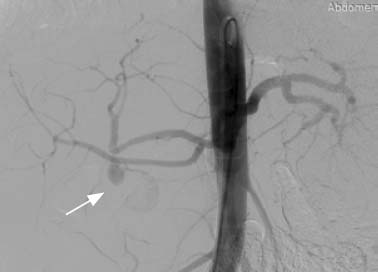

Пациентки были переведены в медицинский центр из других медицинских организаций с установленным диагнозом и причиной желудочно-кишечного кровотечения, после дистанционной консультации сердечно-сосудистого хирурга. Состояние при госпитализации у всех пациенток расценено как тяжёлое. Причиной желудочно-кишечного кровотечения была ложная аневризма ветвей чревного ствола. В табл. 1 показано, что у 10 пациенток диагностирована ложная аневризма желудочно-двенадцатиперстной артерии, у 2 — ложная аневризма селезёночной артерии. Диагноз был установлен при компьютерной томографической ангиографии брюшной полости. На рис. 1 представлена компьютерная ангиограмма брюшного отдела аорты, на которой стрелкой указана ложная аневризма желудочно-двенадцатиперстной артерии.

Рис. 1. Компьютерная ангиограмма брюшного отдела аорты. Стрелкой указана ложная аневризма желудочно-двенадцатиперстной артерии